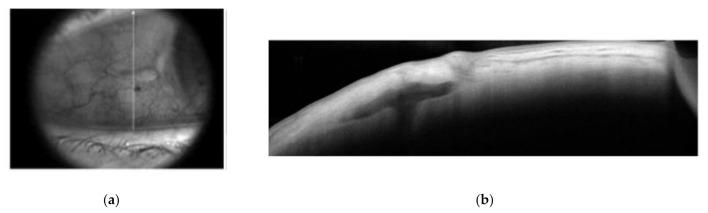

Patients who underwent secondary implantation from December 2019 to January 2021 in the Department of Ophthalmology of Creteil Hospital, and in the Granville Ophthalmology Center, were retrospectively included. Eyes implanted with the iris claw lens (Artisan Aphakia IOL model 205, Ophtec BV, Groningen, The Netherlands) were included in group 1, and eyes implanted with a newly developed sutureless trans-scleral plugs fixated lens (STSPFL, Carlevale lens, Soleko, Pontecorvo, Italy) were included in group 2.

回顾性纳入2019年12月至2021年1月在克雷泰伊医院眼科和格兰维尔眼科中心接受二期植入手术的患者。植入虹膜爪状人工晶状体(荷兰格罗宁根Ophtec BV公司的Artisan Aphakia IOL 205型号)的眼睛纳入第1组,植入新开发的无缝线经巩膜塞固定人工晶状体(STSPFL,意大利蓬泰科尔沃Soleko公司的Carlevale人工晶状体)的眼睛纳入第2组。